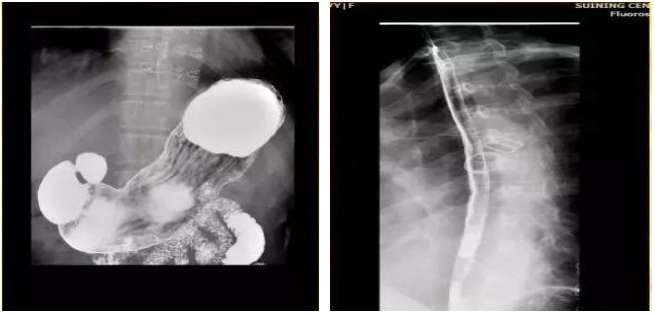

根据其名字一个是钡,一个是餐,钡是指硫酸钡,餐是一顿餐食,其意思是把硫酸钡像饭一样的吃下去。目的是为了充盈胃肠道,让它更加清楚地显示。常用的钡餐为硫酸钡,不溶于水,不会被人体吸收,对人体无害。

钡餐检查的优点是快捷、方便、无创、痛苦小,比较适合不能耐受胃镜检查的病人。但是钡餐是间接影像,比胃镜的检查准确性低一些,而且钡餐不能做组织病理活检,所以如果在做钡餐时考虑有肿瘤的可能性,需要做胃镜进一步检查,取组织病理活检。